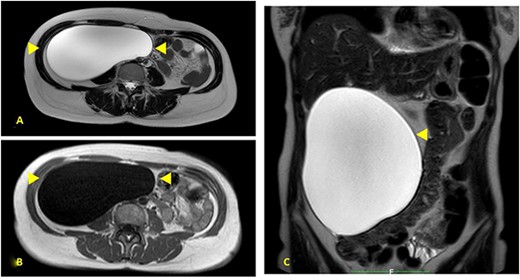

A 52-year-old female was visited at our outpatient service on November 2021 for increasing back pain (4.5 points in the Pain Scale Chart) and the presence of a huge palpable mass occupying the entire right abdomen; she complained of a decade history of recurrent abdominal pain and repeated ultrasound (US), revealing an increasing abdominal cystic-like bulk with fluid content (18 × 8.5 cm. at last US). Neither previous abdominal surgery nor significant familiarity was referred; canalization and food intake were described as regular. At physical examination, a large mass occupying right abdomen could be easily detected; basic laboratory panel and tumoral markers were within range, while body mass index and KPS were, respectively, 21.2 and 90%. Angio-computed tomography (CT) scan revealed a ‘Gross oval-shaped mass with clear fluid content (10–15 HU) and regular margins, measuring 15 × 10 cm. in maximum axial diameter and cranio-caudal extension of ~20 cm, surrounded by a thin hyperdense wall in the absence of intralesional enhancement on delayed phase’ (Fig. 1A). Several structures were displaced as an effect of tumoral enlargement (lower aspect of the right kidney, inferior vena cava, right psoas muscle, gallbladder, right ascending colon, some jejunal loops, head of the pancreas and common bile duct; Fig. 1B). The entire right abdomen resulted as occupied by this huge cystic lesion, which caudally reached the homolateral iliac space. At Prohance® MR, both T1- and T2-weighed sequences confirmed main radiological findings (size 15 × 20 cm, thin aspect of envelope, absence of infiltrative aspect and gross displacement of surrounding structures; Fig. 2A–C). On these bases, preoperative diagnosis of simple mesenteric cyst was hypothesized and the patient was addressed to surgical treatment. Hybrid open-laparoscopic approach was planned: peritoneal space was reached via a midline of 4-cm supraumbilical access and a wall protector-retractor device (Alexis®—Applied Medical) was positioned. Cystic wall lied just beneath surgical access: after a 2/0 Vicryl 2/0 purse string, cyst was incised and 1600 ml of clear-watery content was removed and sent for cytology. Cystic envelope was sharply dissected from ascending colon (Fig. 3A) and was reintroduced into the abdomen. After closing the Alexis® device, a 12-mmHg pneumoperitoneum was induced with the positioning of the 10-mm Alexis® trocar and 2 5-mm working cannulas. Deepest aspect of the cystic wall was completely dissected from the hepatic flexure of the colon and from the second duodenal portion by using a US device and the specimen was removed and sent for histological examination (Fig. 3B). Post-operative was uneventful and the patient was discharged on the second post-operative day. Cytology result was negative for malignancy; at histological examination, a thin-walled cystic formation, translucent at macroscopical appearance was described. Maximum diameter of the empty lesion was 15 cm. Definitive diagnosis was ‘simple serous cyst of the mesentery’ (IHC staining Calretinin−; CD10−).

(A) Prohance® MR; main lesion appears hyperintense on T2-weighted sequences (arrowheads); (B) main lesion appears hypointense on T1-weighted sequences (arrowheads); (C) coronal T2-weighted sequences confirmed main radiological findings: size 15 × 20 cm, thin aspect of envelope, absence of infiltrative aspect and gross displacement of surrounding structures.